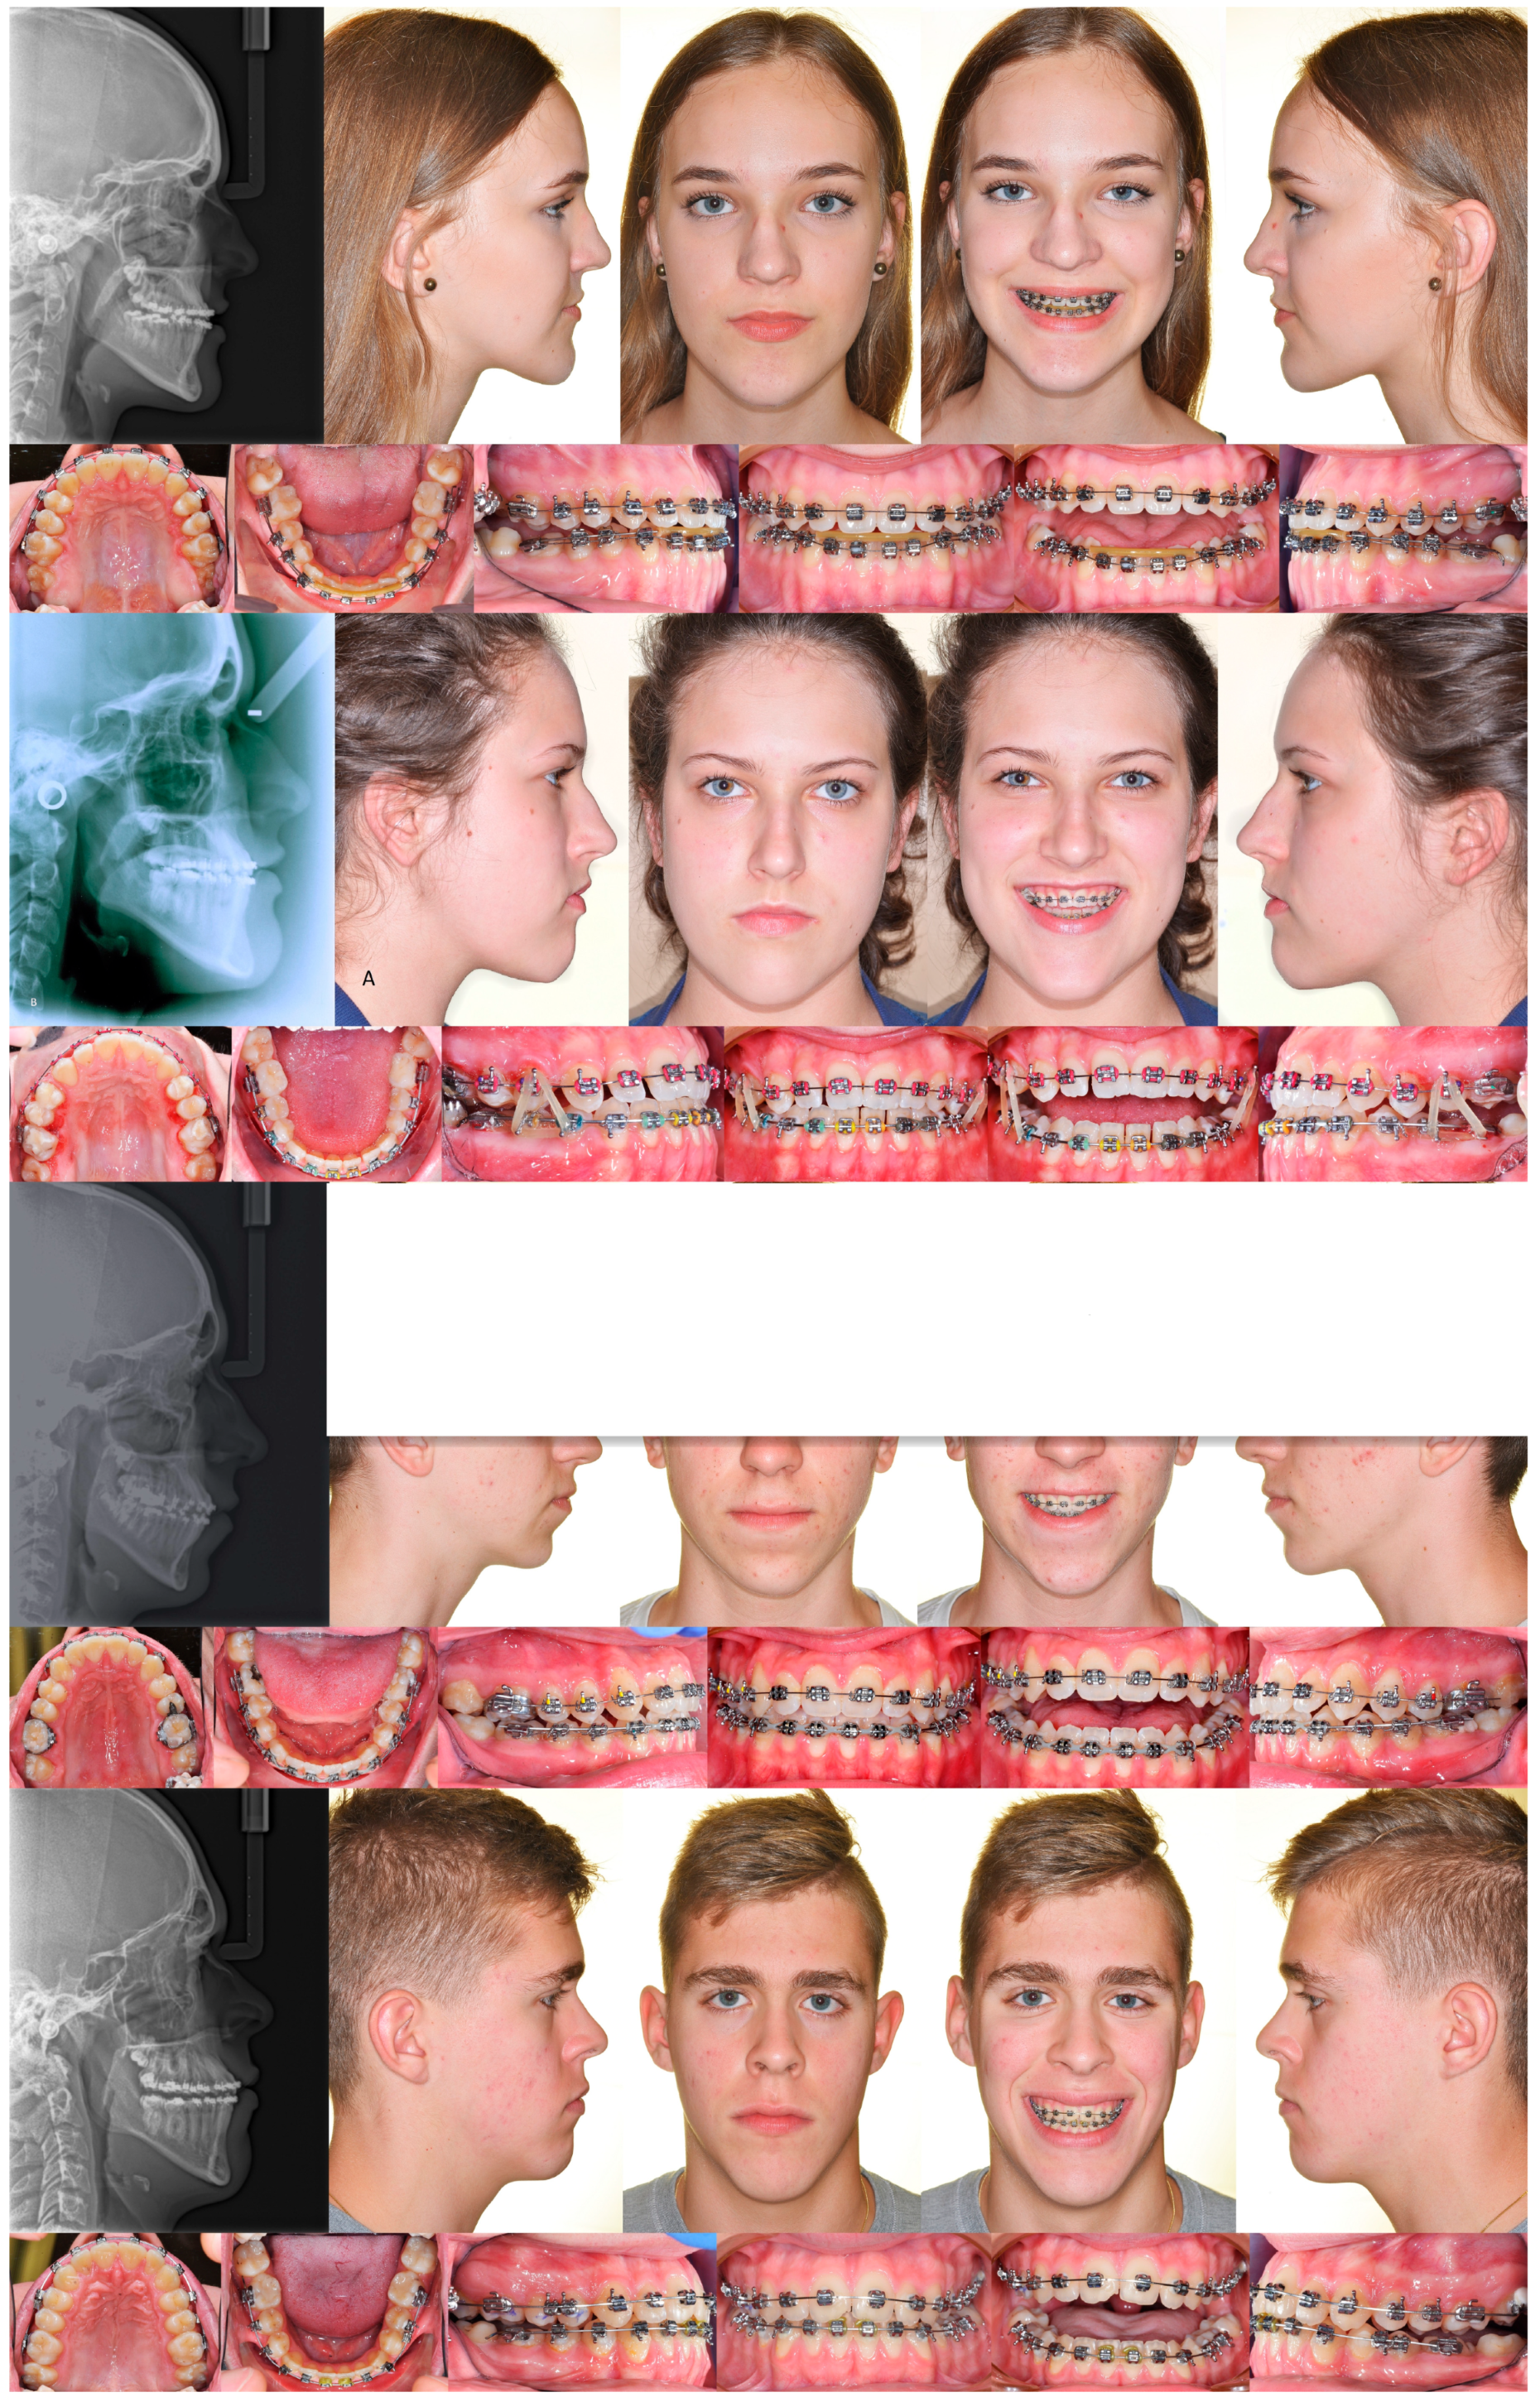

3. The Results of the Treatment